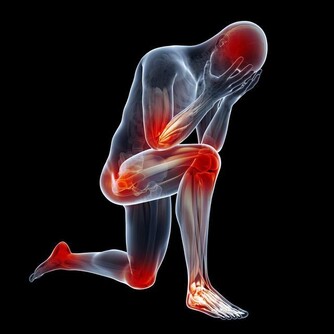

上次回老家,老家有人過來,找我看一眼手,患者手上纏著自己做的白布,膿水已經透過白布滲出來了,我打開了白布,看到裡面潰爛成一片,有兩個一元錢硬幣那麼大的傷口,患者本身是血糖高,但是患者自己吃藥又不及時,最近這段時間自己把藥停了,血糖高,又有傷口,就潰爛了。我問了病史,患者最開始的時候,只有2平方毫米那麼大的小口子,但是就是不癒合,最後發展成這麼大的。

這個患者在找我治療之前,自己用偏方試過,用過偏方之後,導致傷口擴大,我看了患者用的藥物,有輕粉,白礬,紅丹等中醫的收濕斂瘡生肌藥。

這是我非常痛心的一點,這些藥物雖然是中醫收濕斂瘡生肌的藥物,但是這些藥物很多是有毒的,同時患者本身潰爛已經很嚴重了,這些藥物是不適宜直接在潰爛的表面上敷用的,我一方面很心疼患者早點到正規的地方治療就不用受這麼多苦了,一方面痛心很多人對於糖尿病患者皮膚破潰護理知識的匱乏。